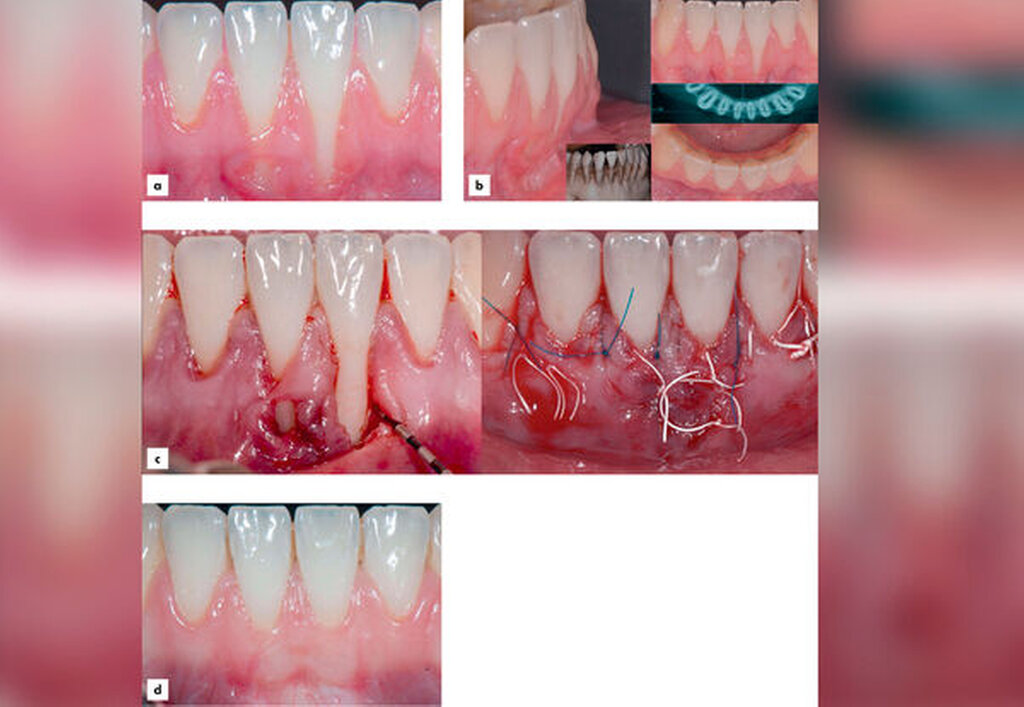

Rezessionsdeckung: Zur chirurgischen Therapie singulärer und multipler Rezessionen ist eine Vielzahl von Techniken entwickelt und in randomisierten Studien (RCTs) untersucht worden. Darauf basierende systematische Übersichten – häufig mit Metaanalysen – sind in den vergangenen 20 Jahren vielfach angefertigt worden, um immer wieder aktuelle Studien berücksichtigen zu können. Dabei konnte überzeugend demonstriert werden, dass mit einigen Techniken vorhersagbar sehr gute Ergebnisse erzielt werden können [Cairo et al., 2014; Graziani et al., 2014; Tonetti & Jepsen, 2014; Chambrone & Tatakis, 2015; Chambrone et al., 2018; 2019]. In den meisten RCTs wurde der Koronale Verschieblappen (KVL) allein oder aber im Vergleich zu KVL plus Bindegewebstransplantat (BGT), ADM, XCM oder Emdogain (EMD) untersucht.

Techniken, die BGT verwenden (mit KVL oder Tunnel) zeigen im Vergleich die besten Ergebnisse hinsichtlich mittlerer und kompletter Rezessionsdeckung und zugleich einer Verbreiterung des keratinisierten Gewebes.

Bei der Interpretation dieser sehr positiven Ergebnisse ist allerdings zu beachten, dass die allermeisten Studien nur Rezessionen ohne interdentalen Attachmentverlust (Miller-Klassen I und II, Cairo-Klasse RT1) eingeschlossen haben (Abbildungen 3 und 4).

Bisher ist relativ wenig über die Therapie von Weichgeweberezessionen an Implantaten und deren Erfolgsaussichten bekannt. Nur wenige prospektive Studien mit kleinen Patienten- beziehungsweise Implantatzahlen haben die Deckung mukosaler periimplantärer Rezessionen untersucht [Bassetti et al., 2017; Mazzotti et al., 2018]. Die Ergebnisse, die an singulären Implantaten ohne periimplantäre Erkrankung mit koronalen Verschiebelappen in Kombination mit BGT erreicht wurden, zeigten eine mittlere Rezessionsdeckung zwischen 66 und 96 Prozent [Zucchelli et al., 2013; Burkhardt et al., 2008; Roccuzzo et al., 2014]. Im Fünf-Jahres-Follow-up zeigten zwei Studien eine mittlere Deckung von 86 beziehungsweise 99 Prozent [Zucchelli et al., 2018; Roccuzzo et al., 2019]. Auch eine retrospektive Fallserie aus einer deutschen Spezialistenpraxis berichtete fünf Jahre nach Therapie mit einem partiell epithelialisierten Bindegewebstransplantat von einer mittleren Rezessionsdeckung von 88 Prozent und einem Gewinn an Höhe des keratinisierten Gewebes [Frisch & Ratka-Krüger, 2020]. Keine signifikante Rezessionsdeckung konnte hingegen bei Verwendung einer xenogenen Kollagenmatrix anstelle eines BGT erzielt werden [Schallhorn et al., 2015].

Nach gegenwärtigem Kenntnisstand können zwei Vorgehensweisen zur Rezessionsdeckung an Implantaten unterschieden werden:

ein rein chirurgischer Ansatz und

ein kombiniert prothetisch-chirurgischer Ansatz, der in jedem Fall die Entfernung und spätere Erneuerung der Krone und gegebenenfalls sogar auch des Abutments mit vorübergehender kompletter Weichgewebsbedeckung des Implantats erforderlich macht [Mazzotti et al., 2018]. Die kombiniert prothetisch-chirurgische Therapie ist deutlich kosten- und auch zeitaufwendiger, allerdings wurden damit bisher die besten Ergebnisse erzielt [Zucchelli et al., 2018]. Die Implantatposition und die Papillenhöhe gelten als Schlüsselfaktoren für die jeweilige Behandlungsstrategie. Deshalb ist in der Klassifikation von Zucchelli et al. [2019], die sich insbesondere an diesen Faktoren orientiert, ein gestaffelter Behandlungsplan in Abhängigkeit von der Schwere des Befunds vorgeschlagen worden. Eine rein chirurgische Therapie kommt demnach nur für die Rezessionsklassen Ia und IIa infrage. Alle anderen Defektklassen erfordern eine kombiniert prothetisch-chirurgische Therapie. Zukünftige Studien werden die klinische Bedeutung und Anwendbarkeit dieses Therapiekonzepts zeigen müssen.